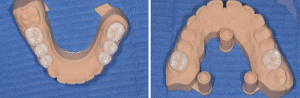

Se référant à la nouvelle DV fixée par le mock-up antérieur et l’enregistrement avec les clés, le laboratoire (LM2M, Paris) usine en PICN les 4 overlays molaires et les 4 veneerlays prémolaires (Fig.9).

Fig.9 : Restaurations postérieures en composite.

Avant d’être essayés en bouche, ils sont stabilisés sur le modèle avec une très fine couche de cire orthodontique et une clé linguale des antérieures mandibulaires est réalisée en silicone.